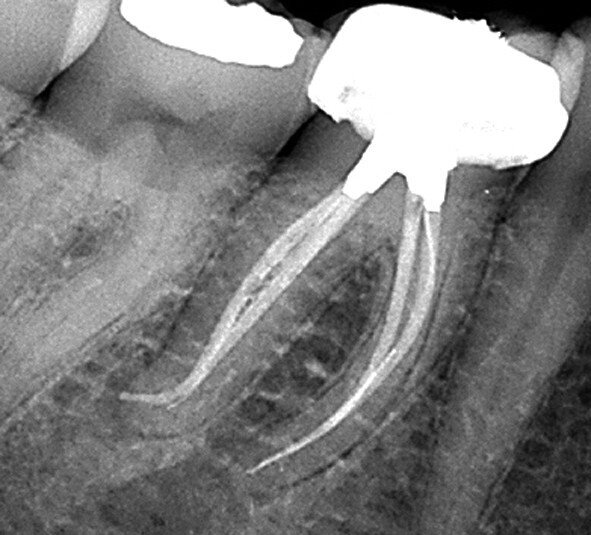

Fig. 7 : Molaire inférieure présentant une calcification presque totale de la cavité pulpaire avant le traitement canalaire, accompli au travers de deux orifices d’accès très précis, laissant entre eux un isthme d’une hauteur de 0,75 mm dans la cavité pulpaire. À noter les résultats finaux du traitement dans les tiers apicaux de chaque canal. (Photo : fournie par le Dr N. Pushpak)